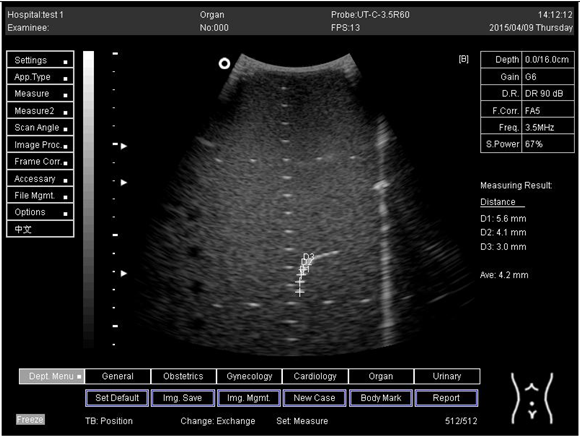

16.0Axial resolution

Biomimetics 07 00130 i025

D1 = 5.6

D2 = 4.1

D3 = 3.0